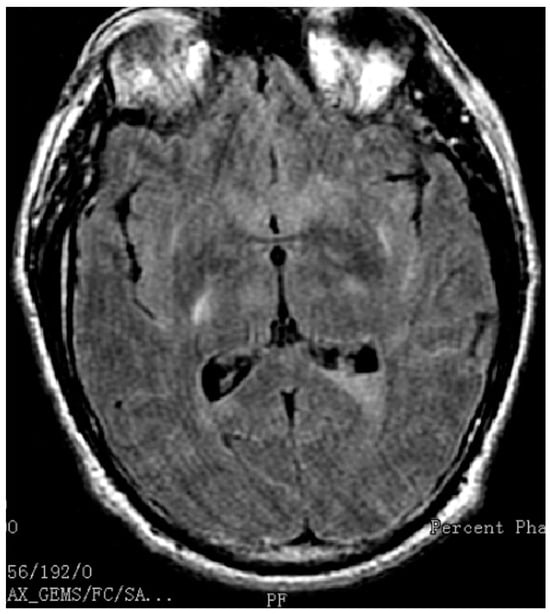

2. Case Report